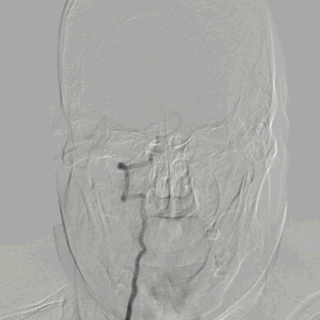

脑血管造影:3型主动脉弓,右侧颈内动脉起始段闭塞,后循环及左侧颈内动脉均未向左侧颈内动脉供血区代偿。

3型主动脉弓,用Mani管超选至右颈总动脉,用260cm加硬泥鳅导丝交换出,在泥鳅导丝导引下,用125cm的多功能管将6F Infinity长鞘置于右颈总动脉,提供稳定支撑。

在Synchro2微导丝及微导管引导下,Catalyst7抽吸导管顺利到达颈内动脉末端。

Catalyst 7抽出大量负荷血栓,大脑中动脉上干仍未显影。

微导丝微导管超选至大脑中动脉上干,微导管造影确认在血管内真腔内,释放Solitaire 4×20mm。

Solitaire 4×20mm支架锚定Catalyst 7抽吸导管到达M1段,抽吸导管负压,拉出取栓支架,取栓过程中Catalyst 7维持稳定。

两次支架取栓取栓取出血栓,血管再通。